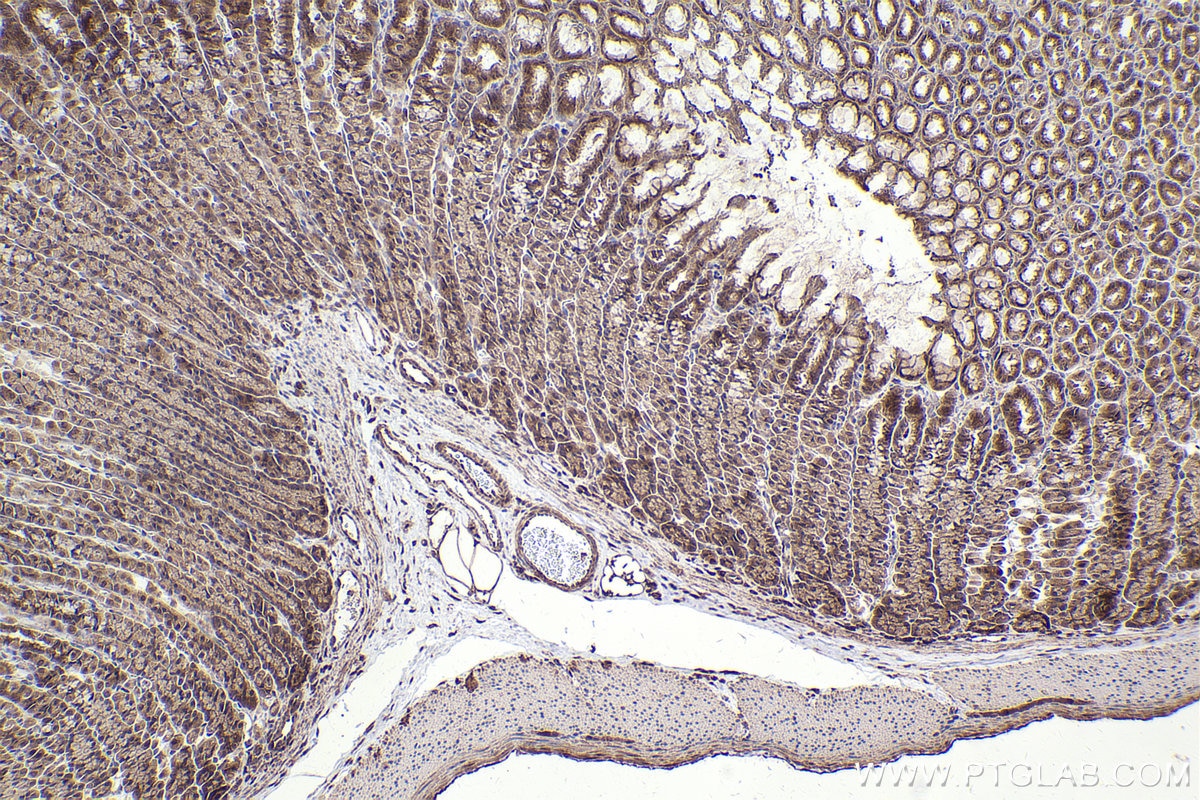

IHCeasy® NFE2L2/NRF2 Ready-To-Use IHC Kit

NFE2L2/NRF2 Ready-to-use reagent kit for IHC.

KHC2502 is a ready-to-use IHC kit for staining of NFE2L2/NRF2. The kit provides all reagents, from antigen retrieval to cover slip mounting, that require little to no diluting or handling prior to use. Simply apply the reagents to your sample slide according to the protocol and you're steps away from obtaining high-quality IHC data.

NRF2, also named as NFE2L2, belongs to the bZIP family and CNC subfamily. It is a transcription activator that binds to antioxidant response (ARE) elements in the promoter regions of target genes. NRF2 is important for the coordinated up-regulation of genes in response to oxidative stress. It may be involved in the transcriptional activation of genes of the beta-globin cluster by mediating enhancer activity of hypersensitive site 2 of the beta-globin locus control region. Nrf2 is a key player in the regulation of genes encoding for many antioxidative response enzymes. The expression of NRF2 may be induced under oxidative stress. In lung cancer, Nrf2 activation in malignant cells has been associated with tumor progression and chemotherapy resistance. Identifying patients with abnormal NRF2 expression may be important for selection for chemotherapy in NSCLC.